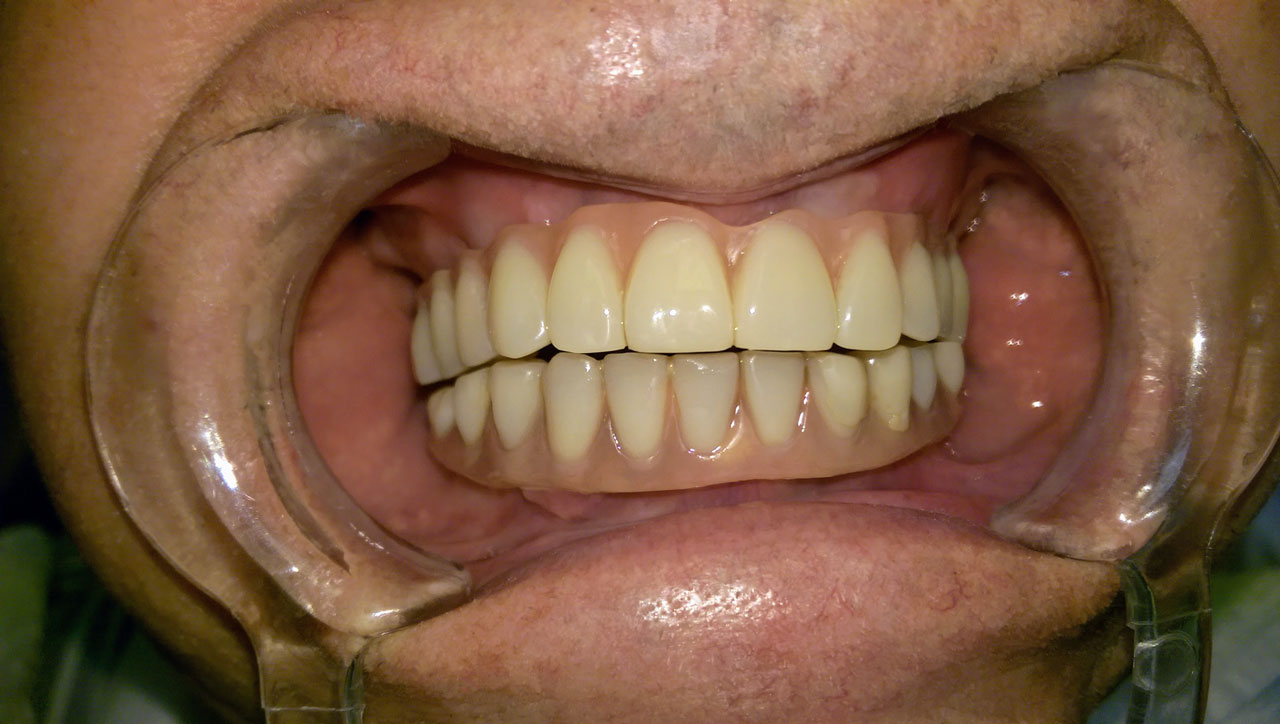

Teljes fogatlanság helyreállítása 2 nap alatt

Teljes fogatlanság helyreállítása 2 nap alatt azonnal terhelhető svájci IHDE implantátumokkal és PMMA műanyag hidakkal. Intraorális szkennerrel vettünk lenyomatot az implantáció után, és erre a digitális mintára készítette el a fogtechnika a hidak digitális tervezését, majd faragta ki műanyagból. Ezt a gyors munkát az azonnal terhelhető implantátumok és a digitális lenyomat, tervezés segítségével tudtuk megcsinálni mindössze 2 nap alatt. Dr. Kelemen Péter és a Symbion Fogtechnika munkája.